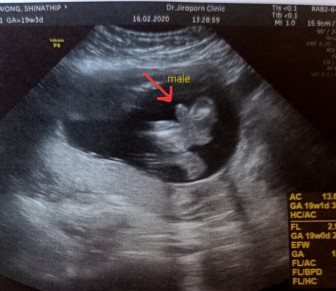

ชายค่ะ 15 ก.ค

ชายค่ะ15ก.ค.